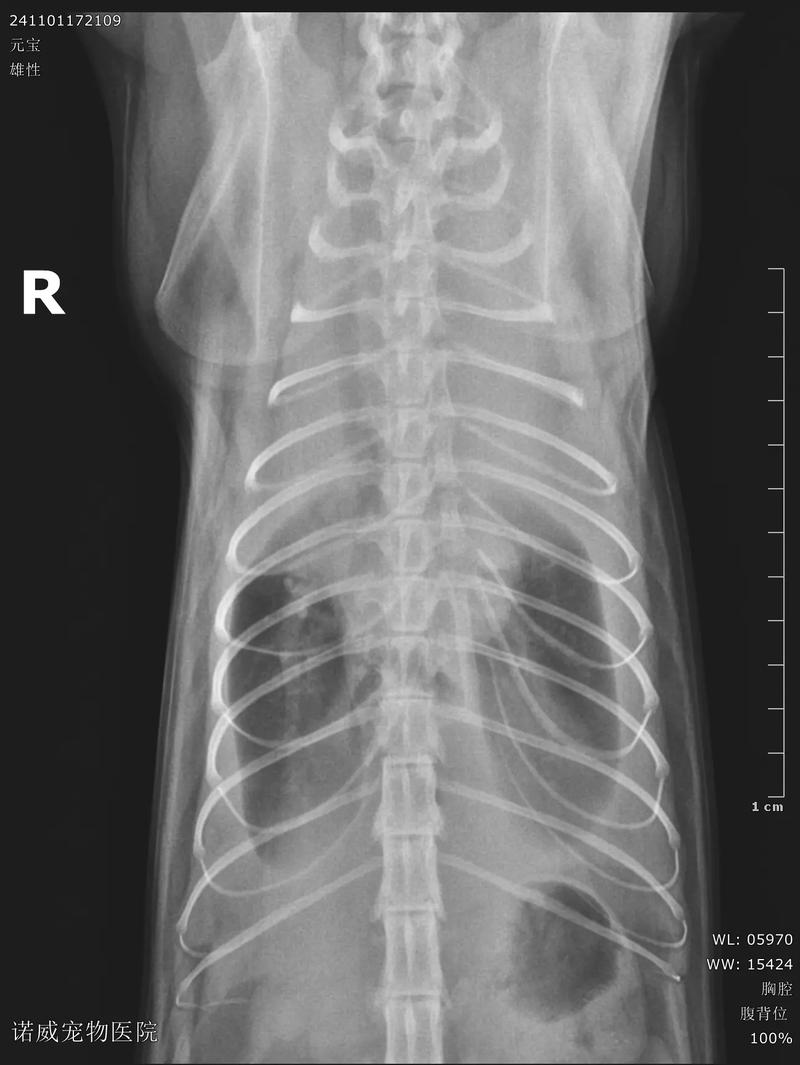

猫咪胸腔积水是有救的,但是需要注意以下问题,第一:胸腔积水是由于受外伤、器官病变等导致胸腔渗透压的改变,使循环中的体液聚集在胸腔,会严重影响猫咪呼吸和心跳。第二:需要进行X光检查确诊胸腔积水的具体情况,此外再进行手术治疗,术后输液比较好添加白蛋白。

猫咪胸腔积水是有救的,关键在于及时的诊断和有效的治疗。诊断方面:全面检查:通过对猫咪的心脏和呼吸功能进行全面评价,有助于对胸腔积液作出初步诊断。一般检查包括站立或胸卧位时的叩诊和听诊,观察心音和肺下部呼吸音的变化。胸膜腔穿刺:这是确诊胸腔积液的重要步骤。